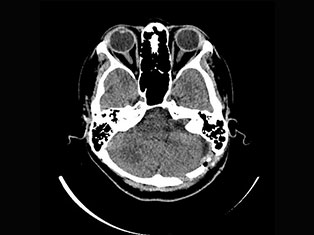

Cerebro Vascular

A stroke occurs when the blood supply to part of your brain is interrupted or reduced, preventing brain tissue from getting oxygen and nutrients. Brain cells begin to die in minutes. A stroke is a medical emergency.